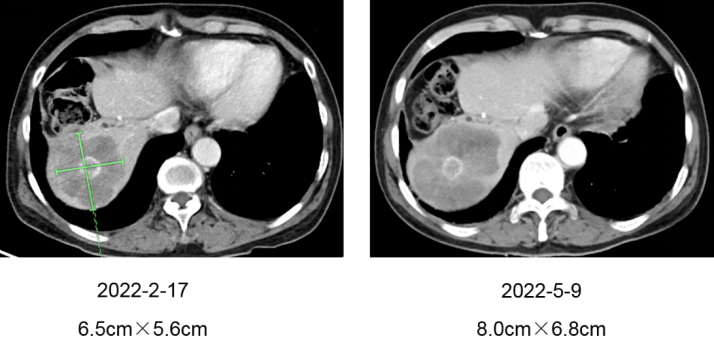

2022-2-23至2022-4-19 再次使用西妥昔单抗+奥沙利铂+雷替曲塞方案治疗4周期,2022-5-9 评估:肝脏病灶再次进展,增大至8.0cm×6.8cm(图三)。

△图三